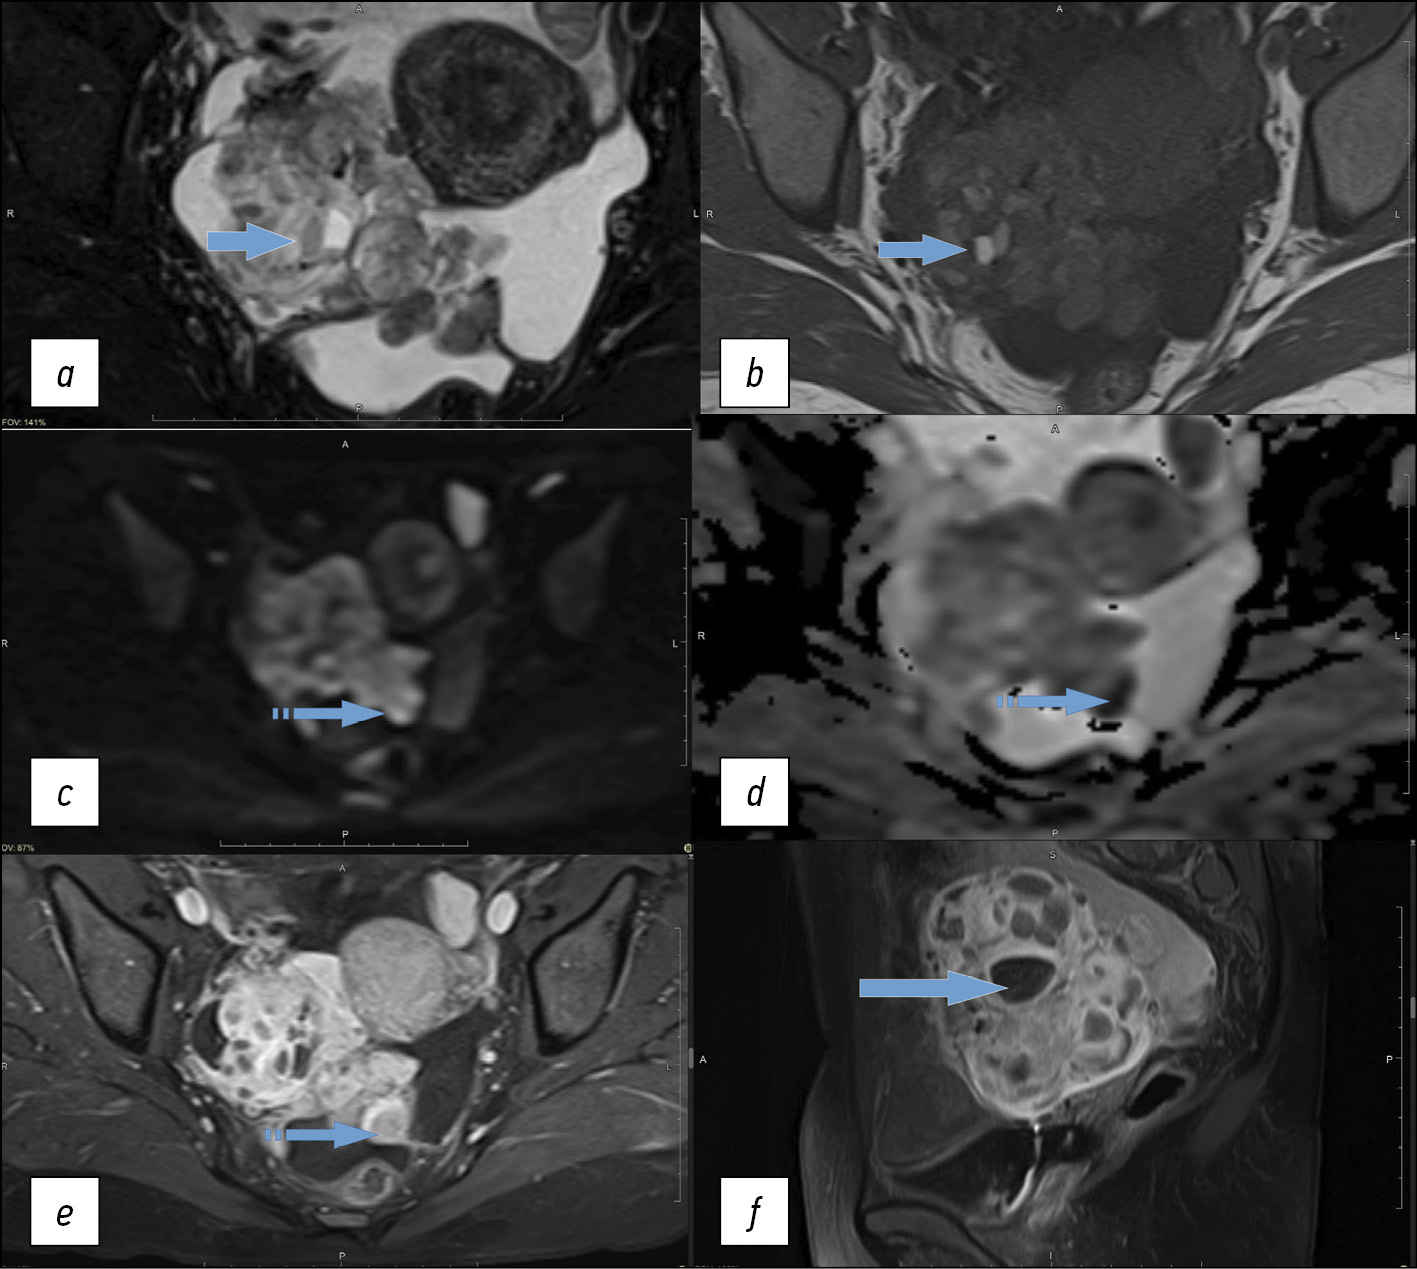

The MRI of the malignant struma ovarii demonstrated a space-occupying predominantly solid mass of the right ovary with uneven poorly defined bumpy edges, areas of multiple cystic inclusions ranging in size from 0.7 to 3 cm with a heterogeneously increased MR signal in T1-WI, heterogeneous (from hyper- to hypo-) MR signal in T2-WI, which was consistent with colloid nodules with high-protein contents of different viscosities. Solid areas of the tumor were characterized by different rates of diffusion restriction, from 0.7 to 1.4 mm2/s × 10–3. Multiple nodular masses along the peritoneum of the small pelvis and diffuse thickening of the peritoneum were also detected. The paramagnetic accumulation in the tumor node along the peritoneum and nodes of the peritoneum was sharply increased in T1-WI, with suppression of the signal from the adipose tissue (Fig. 4). Meanwhile, sagittal post-contrast images clearly show the absence of paramagnetic accumulation in the colloid nodules of the malignant struma of the right ovary (Fig. 4f).

Fig. 4. Pelvic magnetic resonance images of patient R. with malignant struma of the right ovary: (a) T2-FS-WI in the axial plane; (b) T1-WI in the axial plane; (c) diffusion-weighted imaging (b = 1,000); (d) apparent diffusion coefficient map; (e) T1-FS-WI + contrast in the axial plane; (f) T1-FS-WI + contrast in the sagittal plane. The solid arrow indicates colloid nodules in the malignant struma of the right ovary. The dotted arrow shows lesions along the pelvic peritoneum with increased paramagnetic accumulation and restricted diffusion similar to the solid component of the primary tumor.

In the presented case, the tumor did not show typical MRI signs for a malignant struma ovarii; however, the MRI pattern allows suspicion of the inclusions of colloid nodules in the thyroid tissue of the solid component of the ovarian tumor. Varying degrees of restricted diffusion were observed in the solid tumor component and lesions along the pelvic peritoneum. Extremely pronounced paramagnetic accumulation in the solid component of the tumor visualized in the post-contrast series and the absence of accumulation in the colloid nodules were pathognomonic. In the study by Gil et al. [14], MR images revealed struma ovarii as multicystic tumors with solid components, often with high T1-WI signal intensity, whereas cysts had different T2-WI signal intensities depending on fluid viscosity. Tamura et al. [17] analyzed 18 cases of struma ovarii, and their MRI study revealed a solid contrast-accumulating area that corresponded to a malignant variant of the tumor only in 54% of cases; meanwhile, restricted diffusion was established only in 11% of cases.

In the present study, restricted diffusion was heterogeneous but indicated malignant features, given the perfusion parameters in the tumor. Data similar to ours were reported by Yamauchi et al. [7]: the solid component in the malignant struma ovarii was characterized by the increased MR signal in diffusion-weighted imaging and a reduced signal in apparent diffusion coefficient maps. Thus, when compared with a pathomorphological study, the areas of the papillary carcinoma in struma ovarii corresponded to the area of true diffusion restriction in MRI.